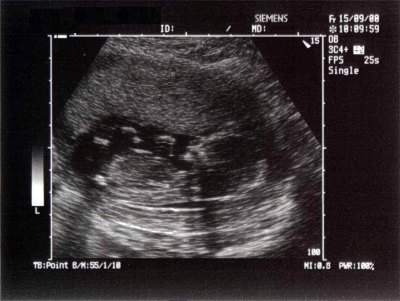

هنا جنينك في الاسبوع الثامن عشر